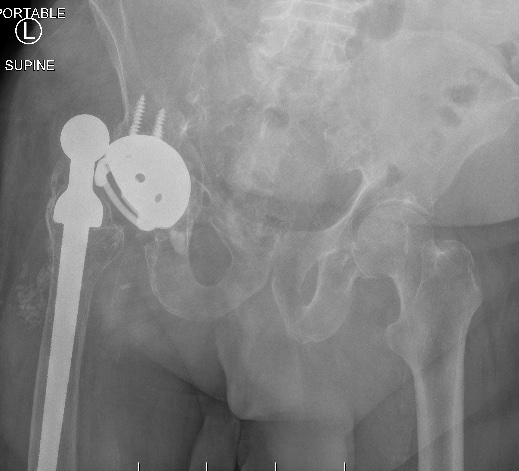

Dislocated constrained liner

Successful reduction constrained liner

Unsuccessful reduction constrained liner